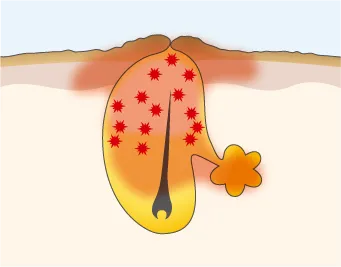

炎症が悪化し膿が溜まる

赤ニキビが進み、膿んでいる状態。ニキビ全体が赤く、毛穴内に膿が溜まり、表面が黄色く見える。

化膿ニキビへと症状が悪化した場合、ニキビの傷が真皮に達し、真皮を破壊してしまいます。

真皮が修復できたところとできなかったところの差が、凸凹となりクレーターになり、元の肌状態に再生するのは極めて難しくなります。また、爪や不衛生な器具でニキビをつぶしたり、力いっぱいニキビをしぼることもクレーターの原因になります。